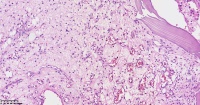

请教老师们这些巨细胞有什么临床意义?

性别

女

年龄

61岁

临床诊断

股骨头骨折

一般病史

标本名称

股骨头组织

大体所见

股骨头骨折处组织

多核吞噬细胞,有纤维素性坏死

是一种反应性改变。